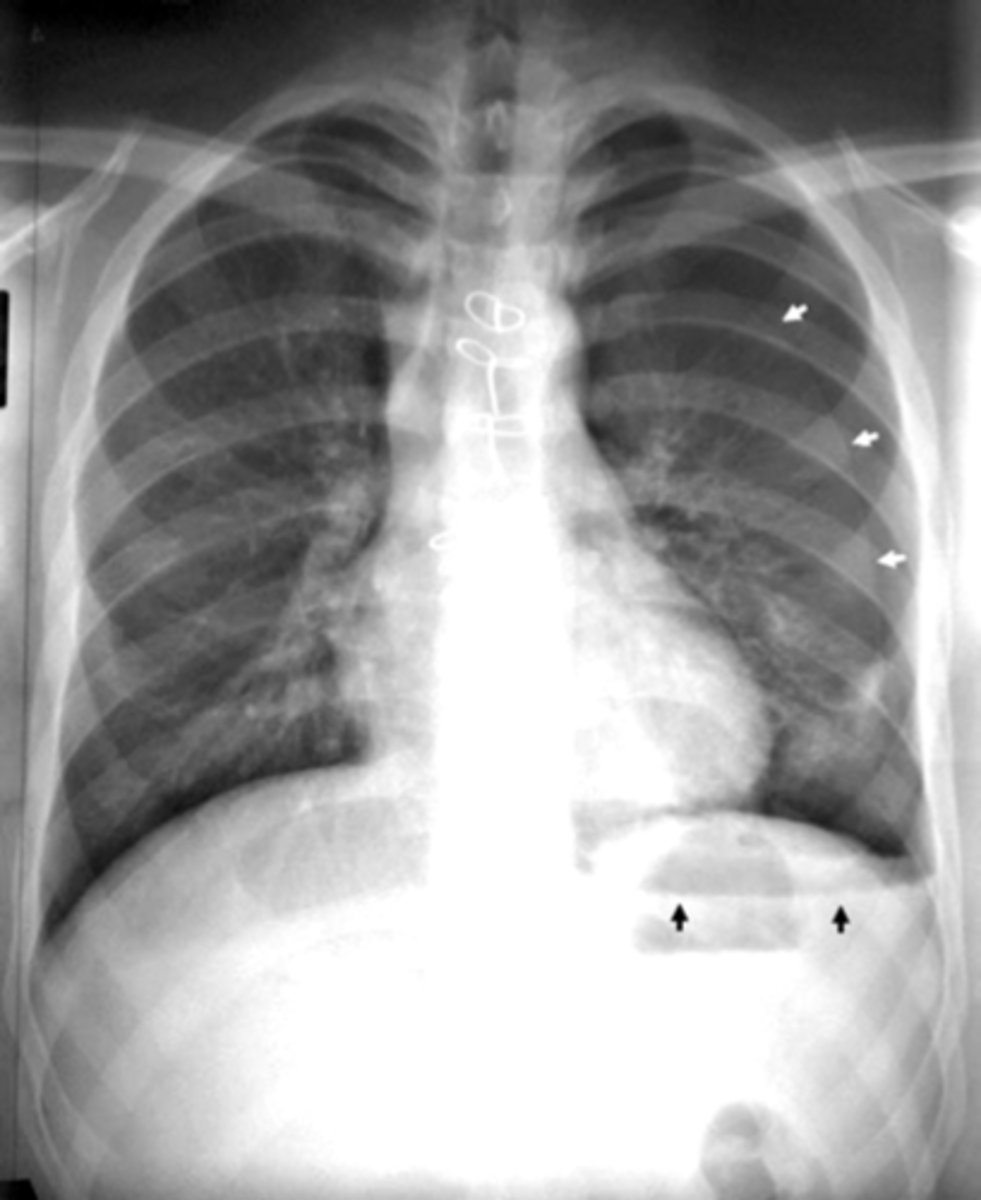

Pneumomediastinum (mediastinal emphysema)

knowt flashcard image

Pneumomediastinum